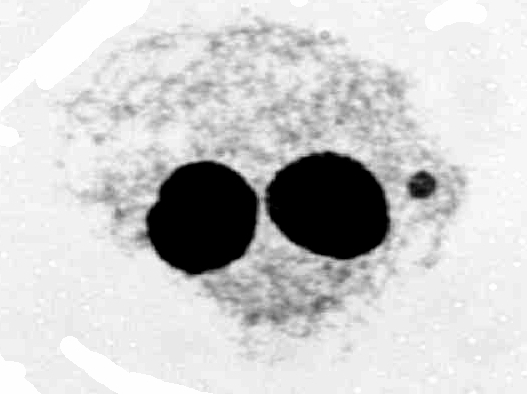

Mikrojádra, obsahující pouze fragment chromozomu (neoznačené, nalevo)  nebo cely chromozom (označené protilátkami specifickými pro centromery, napravo)

nebo cely chromozom (označené protilátkami specifickými pro centromery, napravo)

Citlivost metody lze zvýšit analýzou pouze těch mikrojader, které obsahují fragmenty (což je obvykle výsledkem zlomů DNA během radiace) a vyloučením těch, které obsahují celé chromozomy (které obvykle nesouvisí s ozářením). Tyto dva typy lze rozlišit značením protilátkami specifickými pro centromery (centrální část chromozomu), kde neoznačená mikrojádra zřejmě obsahují pouze fragmenty. Při tomto způsobu se uvádí minimální detekovatelná dávka okolo 50 mGy.